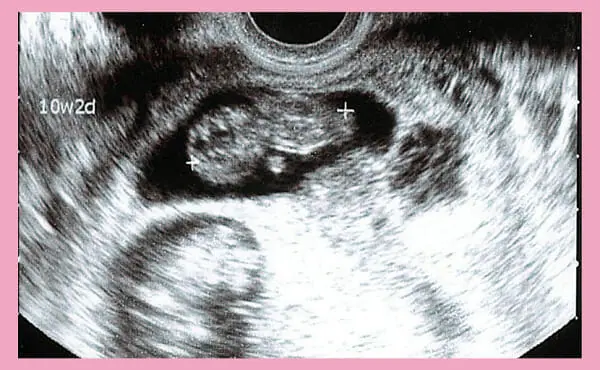

妊娠10週ころにエコー検査(超音波検査)で見ると、赤ちゃんの身体の動きが確認できるようになります。

妊娠10週目のエコー写真です。